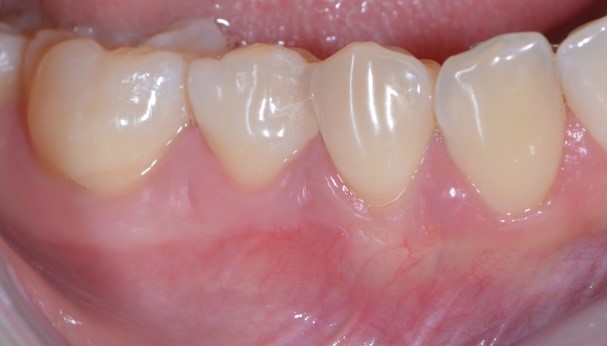

Cosa vedi di strano nella foto qui sotto? Ti sembra che la gengiva di Francesca abbia dei problemi?

Io direi proprio di no e sicuramente tu non puoi che concordare con me. Una bella gengiva rosa e sana.

C’è un trucchetto di mezzo però. Devo confessarti che ho usato Photoshop, ma non per cambiare lo stato di salute dei tessuti (non saprei neanche come fare in verità!!) guarda qui cos’ho fatto…

Ho semplicemente cancellato via i punti di sutura. Sì perché quello è proprio l’aspetto della guarigione a 10 giorni di un lembo a spostamento coronale multiplo con innesto di connettivo prelevato dal palato! Concorderai con me che è un intervento abbastanza “aggressivo”. Si deve scollare un lembo a spessore misto, sezionale le fibre muscolari, spostare coronalmente il lembo, prendere un pezzo di “gengiva” dal palato (qui di solito i pazienti rabbrividiscono) e ficcarla sotto il lembo.